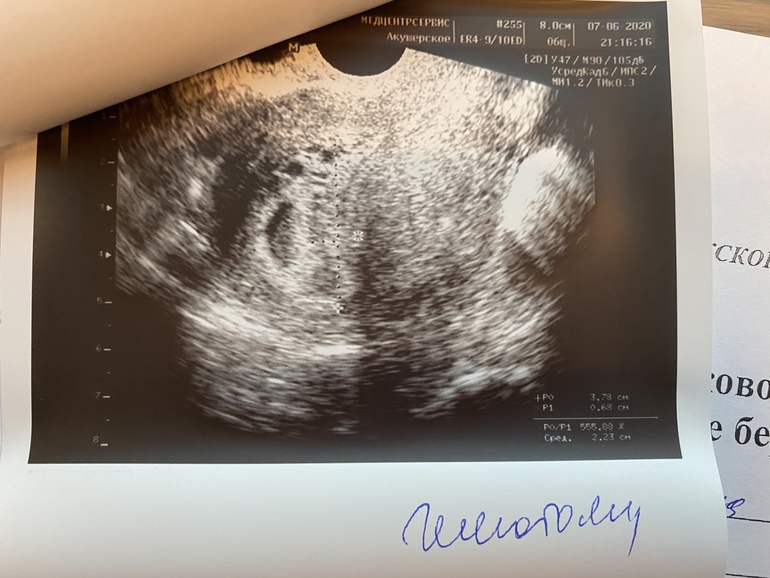

В общем, пока я в панике соображаю как сейчас в 9 часов вечера купить ампулы и найти врачей, которые поставят капельницу на дому, иду в туалет... и тут понимаю что все... приехали! На толчке из меня льет кровь и просто вываливается кусок!! Не кусочек, а кусок! С мою ладонь, тонкая такая, как кусок печени, еще чуть полило и все! Тут же кровить перестала. Я думала, что это собственно оно.... все произошло, если вы поняли о чем я. Фото своих трусов и этого куска я отправила Ре, она сказала это в баночку в физ раствор и холодильник, а мне бы сделать срочное узи. Я уже ни во что не верила, нашла круглосуточное узи рядом с домом, через пять минут была у врача... И вот бывает же так, когда в такие моменты рядом оказываются хорошие люди. Я ни жива ни мертва, на подкашивающихся ногах, легла на кушетку... а она смотрит и говорит... "Зайчик, не волнуйся, все нормально, вот твой эмбрион, вот у тебя гематома какая", включила СБ, я его слышала! 123 удара в минуту, КТР 4,7, ЖМ 3 мм, ПЯ 30 мм. Но гематома есть, на фото узи эндометрий такой разрыхленный... сейчас приложу фото...